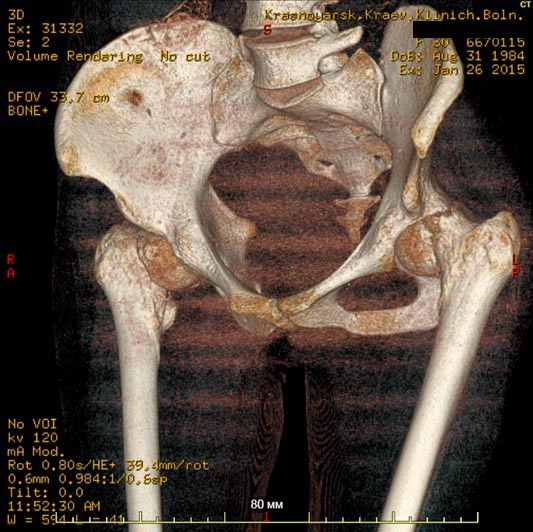

Клинический случай, больная Т. 30 лет, 40 кг, анамнез: Считает себя больной с начала декабря 2014 года, травмы отрицает, ни с чем не связывает. Со слов на фоне полного здоровья появились отеки всего тела, после чего боли в пояснице, правом к/с, затем т/б суставах. Обратилась за мед.помощью по месту жительства, анемия до 40 г/л. Произведена гемотрансфузия эр.взвесью, гемоглобин 100. При обследовании выявлена киста яичника, с подозрением на злокачественный процесс с mts в кости таза пациентка направлена на консультацию к онкологу. Злокачественный процесс исключен.

Направлена на консультацию к гематологу , выполнена стернальная пункция. Данных за миелому не получено. Больная в настоящее время проходит дообследование с перспективой для паллиативного (а может и нет?) протезирования т/б суставов. Из обследований: положительное RW, лечилась 10 лет назад. Гемоглобин 85, снижается, произведена гемотрансфузия до 100, формула б/о. Билирубин общ 47, прямой 9, по УЗИ, ФГС б/о. Т-лимфоциты 60,Т - хелперы - 20. Остальное в пределах нормы, легкие чистые. По МСКТ - дефект правой подвздошной. Как еще обследовать больную? на что похоже? Спасибо заранее за ответы

Не очень понятно насчет патологического характера перелома шеек бедра: на КТ есть локальное разрушение кости?

Кроме очага в подвздошной кости: есть ли другие? В этом может помочь сцинтиография с технецием.